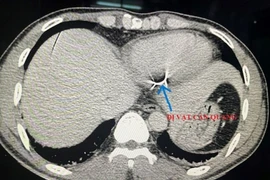

Các bác sĩ bệnh viện Đa khoa Trung ương Cần Thơ đã phẫu thuật gắp đoạn gắp đoạn kim loại dài 4x0,4 cm, máu phun ra thành tia trong tim một bệnh nhân đi cắt cỏ cắt phải dây kẽm gai, dây đứt xuyên vào.